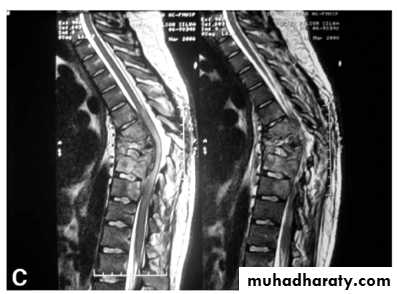

In T B spine

BACKACHE

Kyphosis (gibbus).

Occasionally the presenting feature is weakness or loss of sensibility in the lower limb.

In neglected cases patient presented with paralysis (pott’s paraplegia).

T B spondylitis may appear as localized bone erosion and collapse across an intervertebral disc space

There may be soft tissue traces of paravertebral abscess.